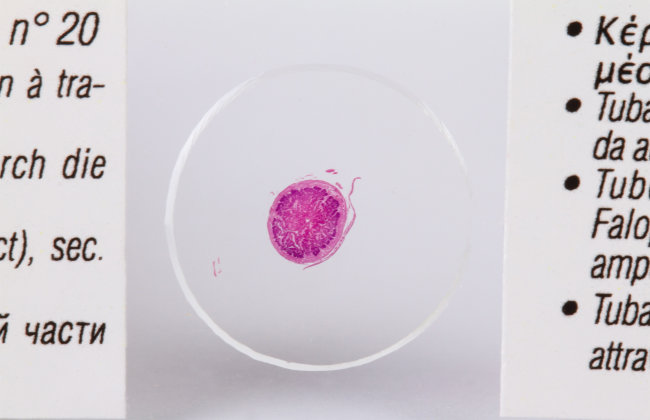

20. Срез ампулярной части яйцевода.